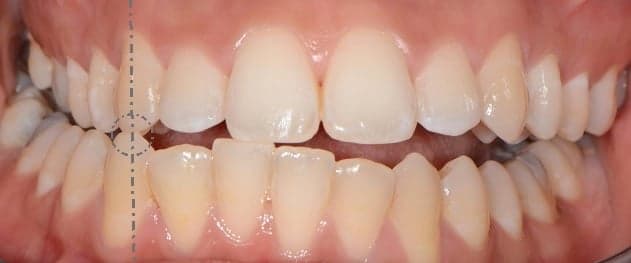

5. 1. 절치 관계

상악과 하악 절치 간의 관계는 Angle의 절치 관계 분류에 따라 다음과 같이 나뉜다.

• '''1급:''' 하악 절치가 상악 절치의 중앙 1/3 또는 설면의 치경에 닿는다.

• '''2급:''' 하악 절치가 구개면에서 상악 절치와 닿으며, 치은 1/3 또는 치경 뒤에 닿는다. 1분할과 2분할로 더 세분화된다.

• '''1분할'''에는 앞으로 뻗은(90%) 상악 절치가 포함되며, 수평피개라고 하는 더 큰 수평 겹침을 가진다.

• '''2분할'''에는 뒤로 젖혀진(10%) 절치가 포함되며, 수직피개라고 하는 수직 겹침이 증가한다.[7]

• '''3급:''' 하악 절치는 상악 절치와 구개면에서, 특히 절단 1/3에서 또는 치경 앞에 교합한다.

• 수평피개가 반전되고(<0mm) 하악 절치가 상악 절치보다 앞쪽에 위치하는 경우도 있다.

5. 2. 구치 관계

후방 치아의 교합을 논할 때, 이 분류는 제1 대구치를 지칭하며 세 가지 범주로 나눌 수 있다.

• '''1급:''' 하악 제1대구치가 상악 제1대구치의 근심에 교합하며, 상악 제1대구치의 근심 협측 교두가 하악 제1대구치의 협측 구에 교합한다.

• '''2급:''' 상악 제1대구치의 근심 협측 교두가 하악 제1대구치의 협측 구 앞쪽에 교합한다.

• '''3급:''' 상악 제1대구치의 근심 협측 교두가 하악 제1대구치의 협측 구 뒤쪽에 교합한다.[5]

치아의 정상적인 관계(1급)에서 벗어나는 모든 것은 부정교합으로 간주된다.